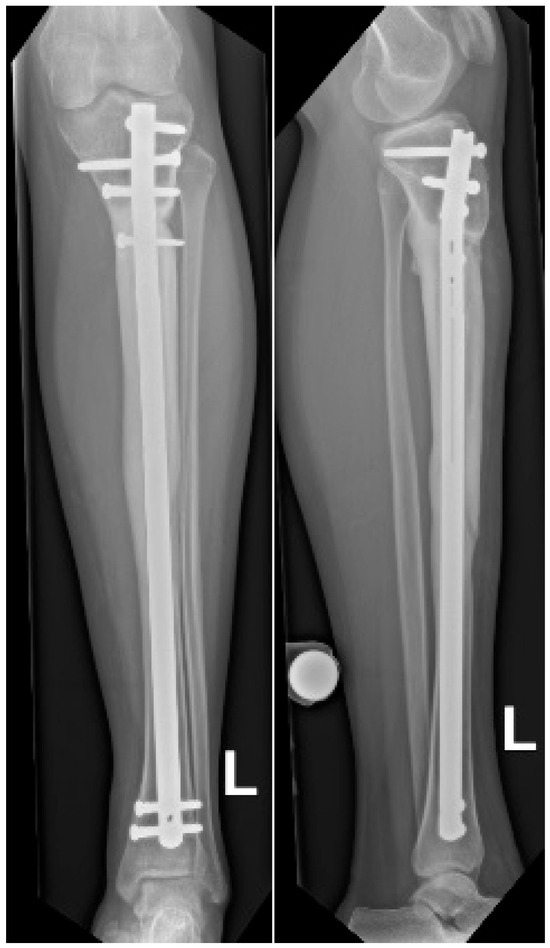

Background: Reconstructing large bone defects in pediatric patients after tumor resection is challenging, as conventional techniques are associated with high complication rates and morbidity. The Intramedullary Bone Transport Nail (IMBTN) may reduce these complications while preserving limb alignment and skeletal growth in pediatric oncologic reconstruction. Methods: A 15-year-old female with an osteofibrous dysplasia-like adamantinoma of the tibial diaphysis underwent complete en-bloc resection, leaving a 9 cm bone defect. An IMBTN (Precice, NuVasive) was implanted for distraction osteogenesis, with distraction starting eight days post-surgery at 0.25 mm twice daily. Follow-up visits monitored bone healing, alignment, and limb length. Results: The 9 cm defect was successfully reconstructed, with complete bone healing at the distraction site. Complete consolidation was confirmed at 18 months. The transport nail was removed at two years, and no further revisions were necessary. At two-year follow-up, the patient reported minimal pain on the Visual Analog Scale 1/10, and no recurrence of the tumor was noted. Conclusions: The use of IMBTN for large bone defect reconstruction following tumor resection in pediatric patients is a safe and effective technique. It enables stable bone transport while preserving alignment, maintaining limb length, and is less invasive than traditional reconstructive approaches. Full article

Figure 1